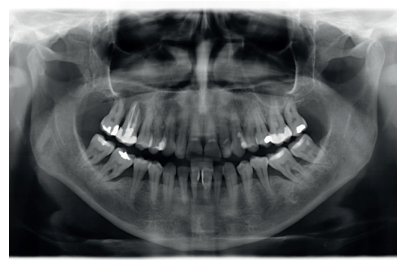

Prevención de defectos periodontales tras la exodoncia de terceros molares inferiores con injerto de dentina autógena: evaluación a 6 meses de un caso clínico

Introducción: El defecto periodontal localizado en la cara distal del segundo molar inferior es una complicación asociada al tercer molar inferior en posición horizontal o mesioangular. El tratamiento quirúrgico de estos terceros molares inferiores retenidos se acompaña del desbridamiento de la cara distal del segundo molar, no siendo esto suficiente para devolver la salud periodontal en esta zona. Por tanto, son muchos los autores que recomiendan la regeneración ósea guiada para conseguir una recuperación periodontal completa.

Caso clínico: Se presenta un caso clínico de una mujer de 27 años de edad, sin antecedentes médico-quirúrgicos de interés, que acudió al Servicio de Cirugía Bucal e Implantología de la Facultad de Odontología de la Universidad Complutense de Madrid para la exodoncia de los terceros molares inferiores. Una vez realizada la Historia Clínica, se le realizó la exodoncia del tercer molar inferior izquierdo en posición horizontal con regeneración con dentina autógena, y el tercer molar inferior derecho de manera convencional, haciendo un seguimiento de 6 meses para comparar la evolución de ambos lados.

Conclusiones: la dentina autógena puede ayudar a la reducción de los defectos periodontales post exodoncia sobre el segundo molar tras la extracción de terceros molares inferiores mal posicionados.